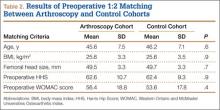

The same registry database was used to identify patients who received an HRA without a prior history of arthroscopy or hip surgery. A 1:2 matching analysis for those patients with a prior hip arthroscopy to those without a prior hip arthroscopy was performed to formulate a control group (control cohort) of 86 patients. Each patient in the arthroscopy cohort was matched with 2 patients in the control cohort based on the following parameters: age (± 6 years), sex (same), BMI (± 4 kg/m2), femoral head size (± 4 mm), and preoperative HHS and WOMAC scores (± 7 points). In the event an arthroscopy patient matched to 2 or more control patients, the patients who minimized the least squared error among the matching variables were selected.

A comparison of the results of the 1:2 matching analysis between the arthroscopy and control cohorts is presented in Table 2. There was no significant difference in the preoperative age, BMI, femoral head size, HHS, or WOMAC score between the 2 cohorts. However, the control cohort did show a more severe, preoperative flexion contracture (as expressed by a decreased amount of extension) and a decreased amount of preoperative abduction (Table 3). The preoperative UCLA activity score was also decreased in the control cohort, but this was not statistically significant.